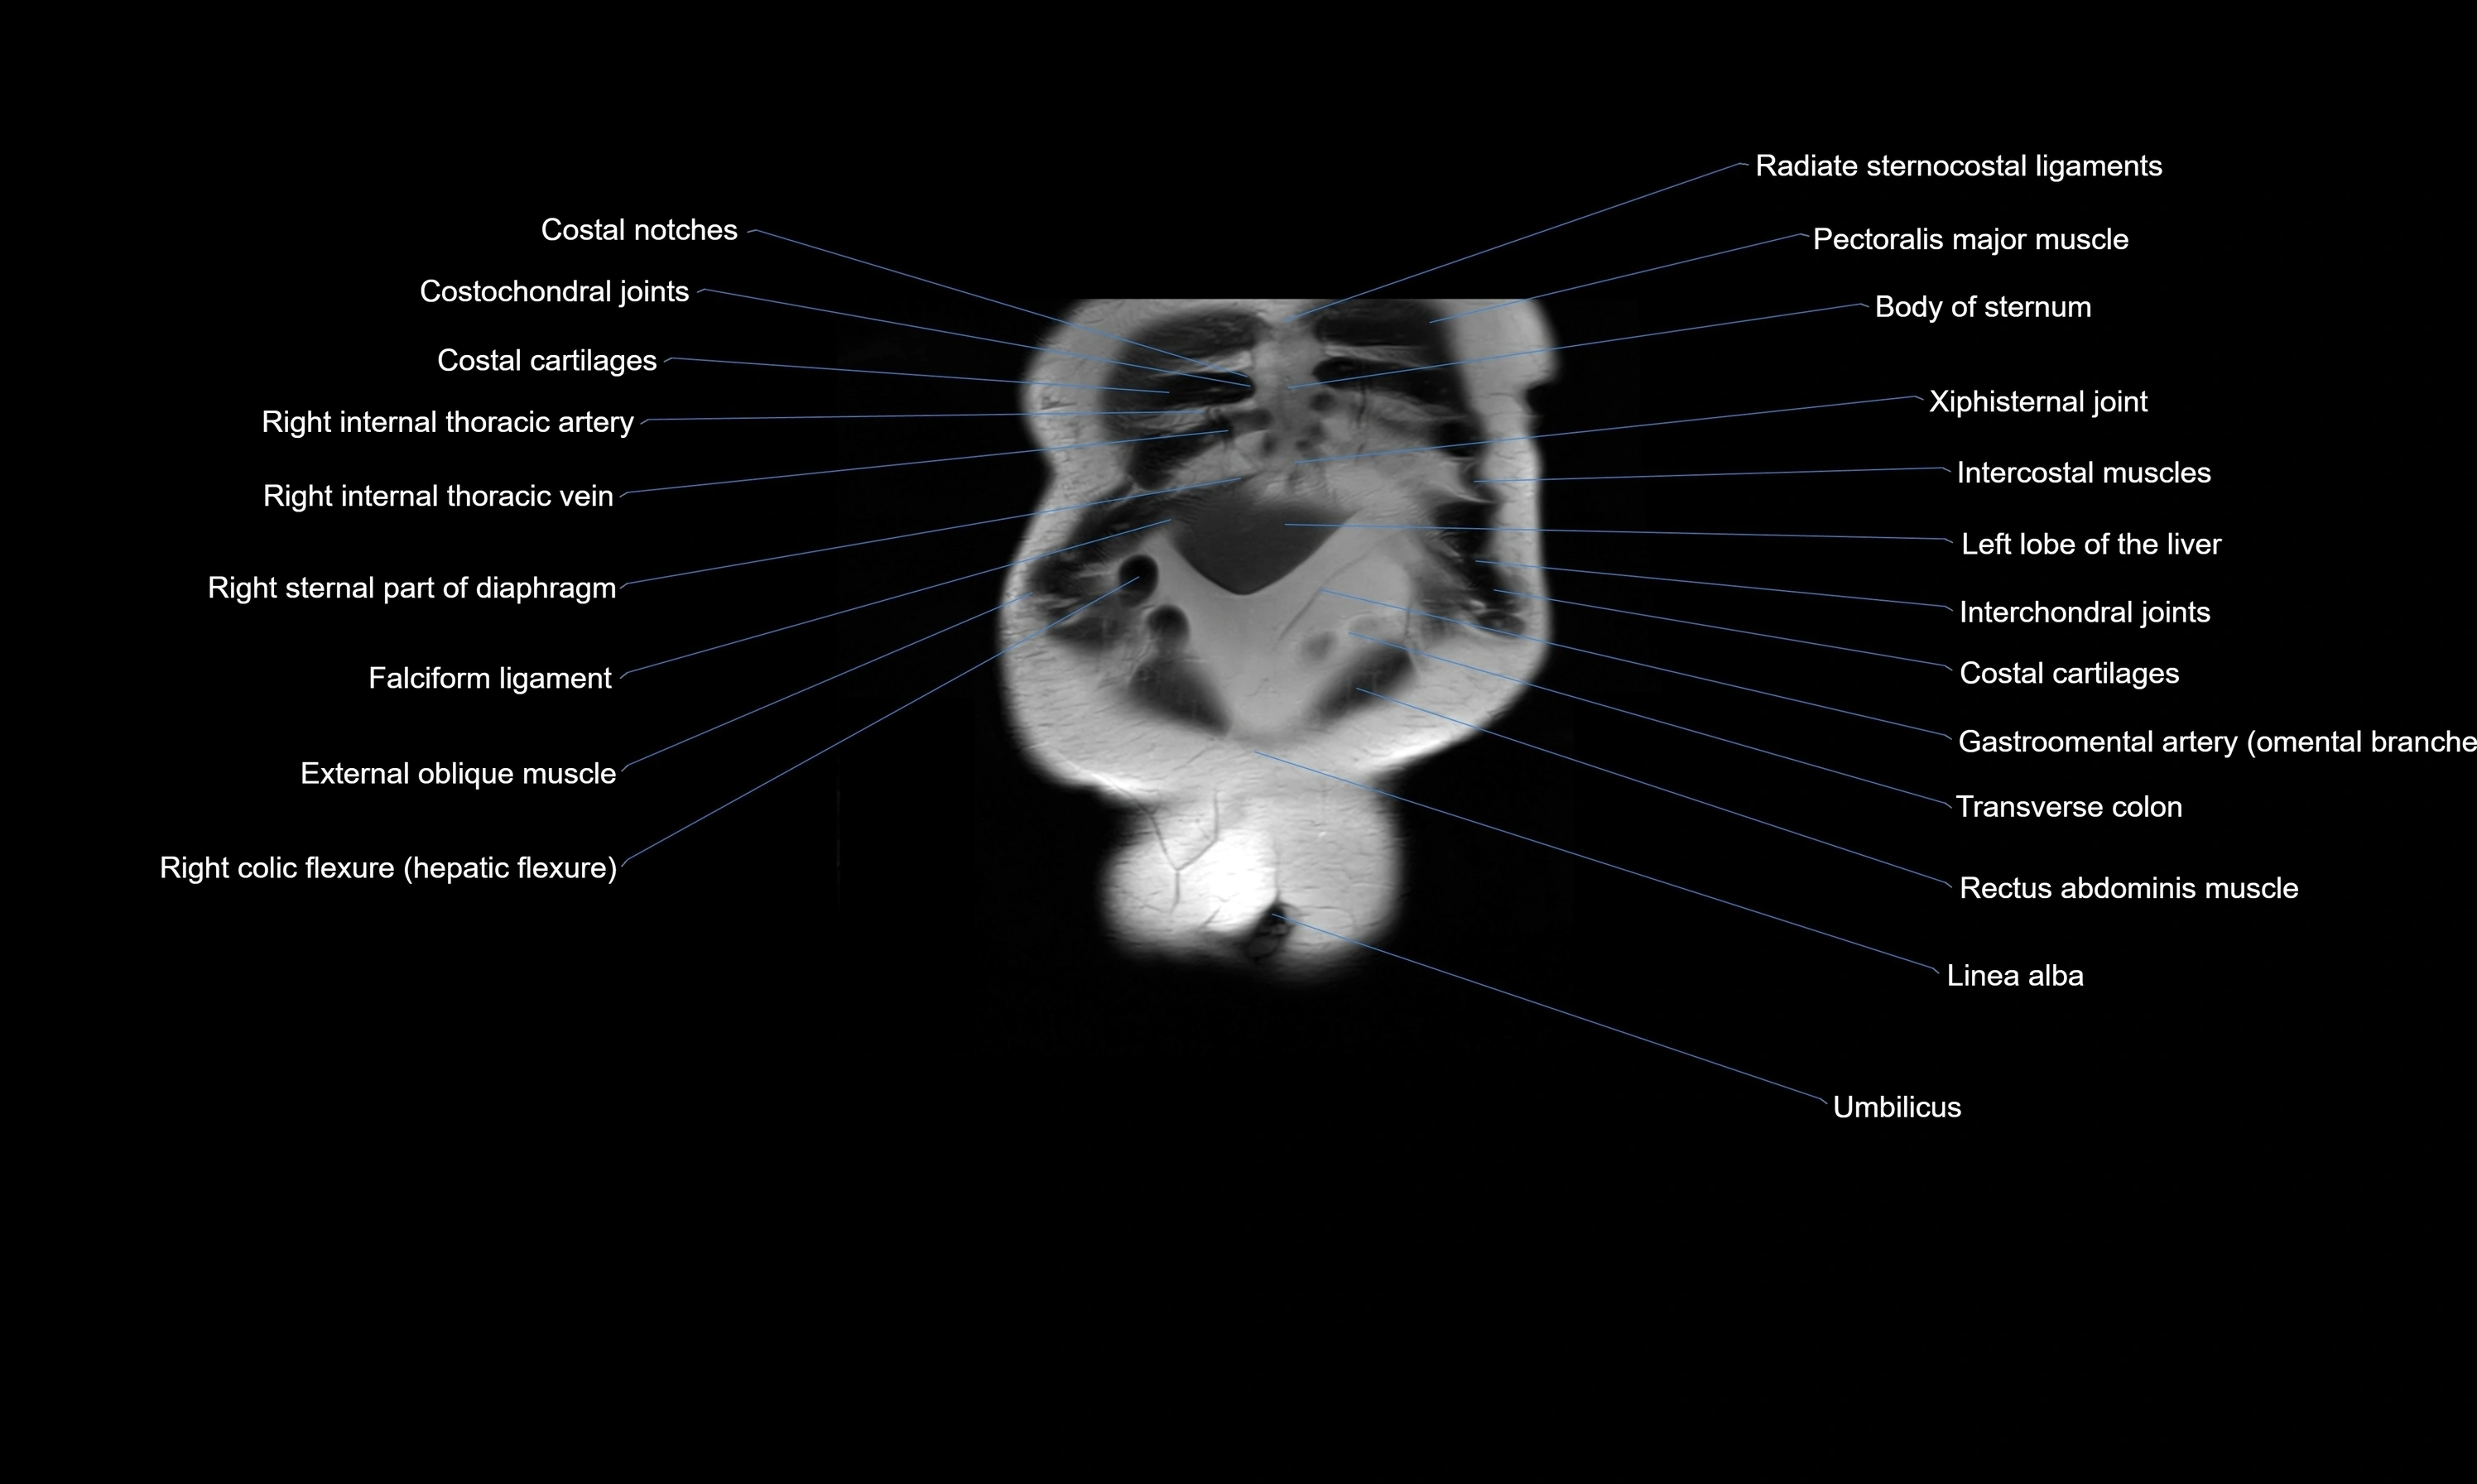

MRI images